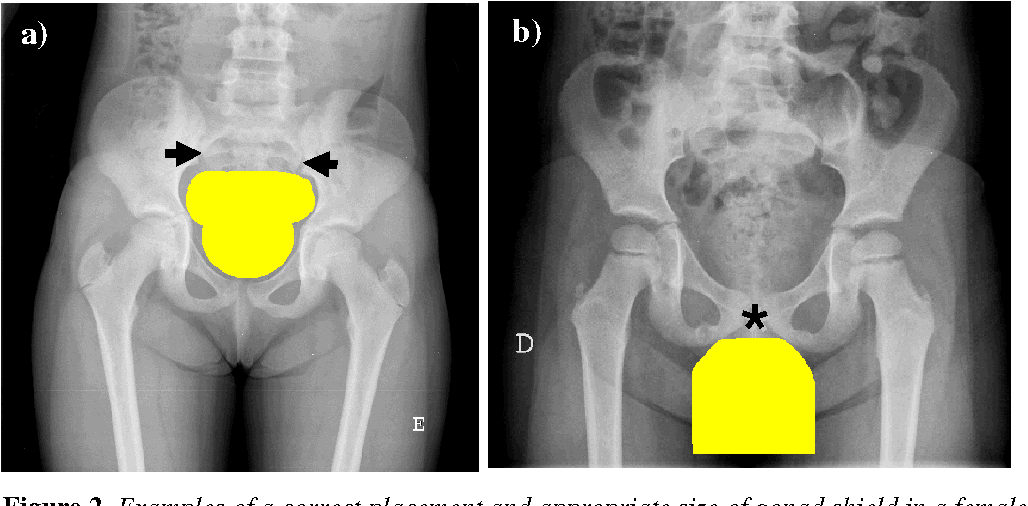

Fetal and Gonadal Shielding Guidelines

May 19, 2021